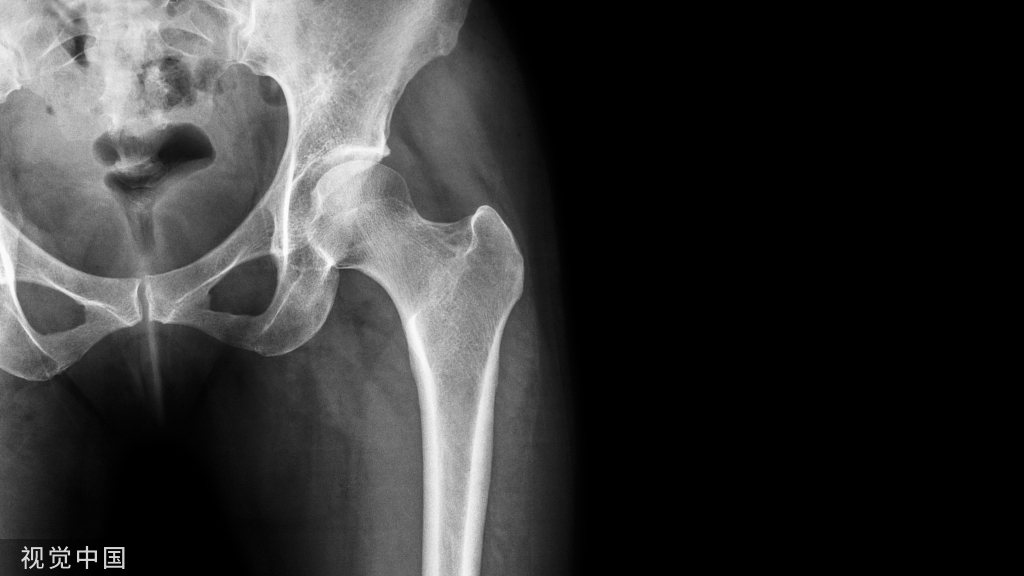

图5 髋关节外侧入路(Watson-Jones入路)

该切口分直切口和弧形切口两种形式,前者以股骨大粗隆为中心,经股骨大粗隆外侧和股骨干外侧至大粗隆远端5cm处纵行切开;后者起于髂前上棘后外侧2.5cm处,弧形向后下延伸,经股骨大粗隆后侧1/3至股骨外侧。该入路经臀中肌及阔筋膜张肌间隙进入(图5)。